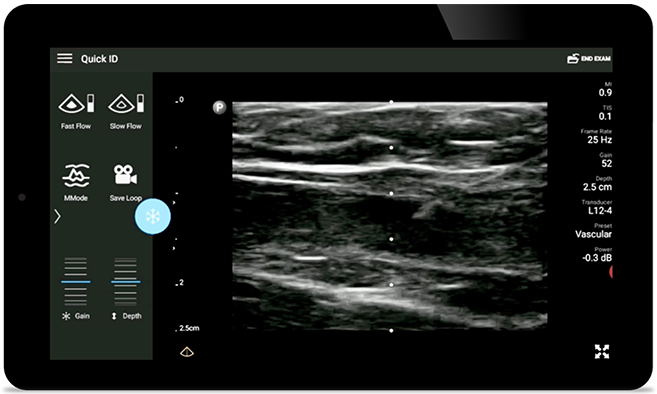

Weniger Komplikationen beim Legen von ZVK

Echtzeit-Ultraschall kann die Genauigkeit und Sicherheit beim Legen von ZVK verbessern.